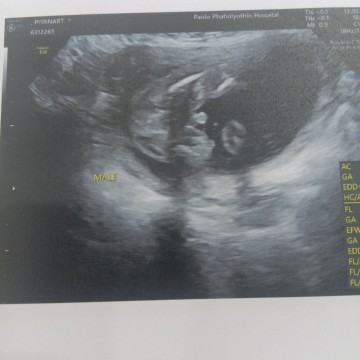

ผมมีจู๋คับ

ผมนอนพับขาอยู่ ผมเป็นผุ้ชาย ร่างกายแข็งแรงดีจ้า แม่ๆบ้านอื่นผู้หญิงผู้ชายจ้ะ???

ซาวน์เมื่อวานนี้ค่ะ ผู้หญิงบ้านนี้ได้สมใจเลยค่ะ พ่อน้องปรบมือเลย ดีใจจนหมอแซว 20+5

บ้านนี้ก็ผู้ชายค้าบ นอนพับขาเหมือนกันเลย เอามือบังหน้าด้วย 😂😂

ผู้ชายค้าาา คุณพ่อยิ้มใหญ่เลย เพราะเห็นจู๋มาแต่ไกล

🤰🏻18W กำหนดสิงหา บ้านนี้ก็ได้ลูกชายค่ะ😍😊

ซาวเมื่อวาน ช. เหมือนกันจ้า 23w. ❤